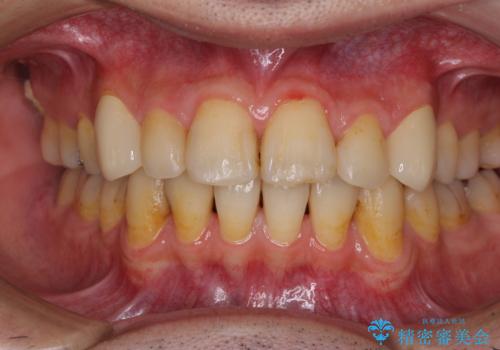

- 以前矯正を行った際に前歯が虫歯だらけとなり、審美面を気にして来院された患者様です。

虫歯の大きかった左右犬歯はオールセラミッククラウンで補綴治療をおこない、4前歯は研磨や古い充填物の詰め直しを行いました。

歯並びは良くなったものの、着色が気になって口元を見せることを躊躇していた用ですが、治療後は他人の視線を気にすることがなくなったようで、大変満足していただきました。